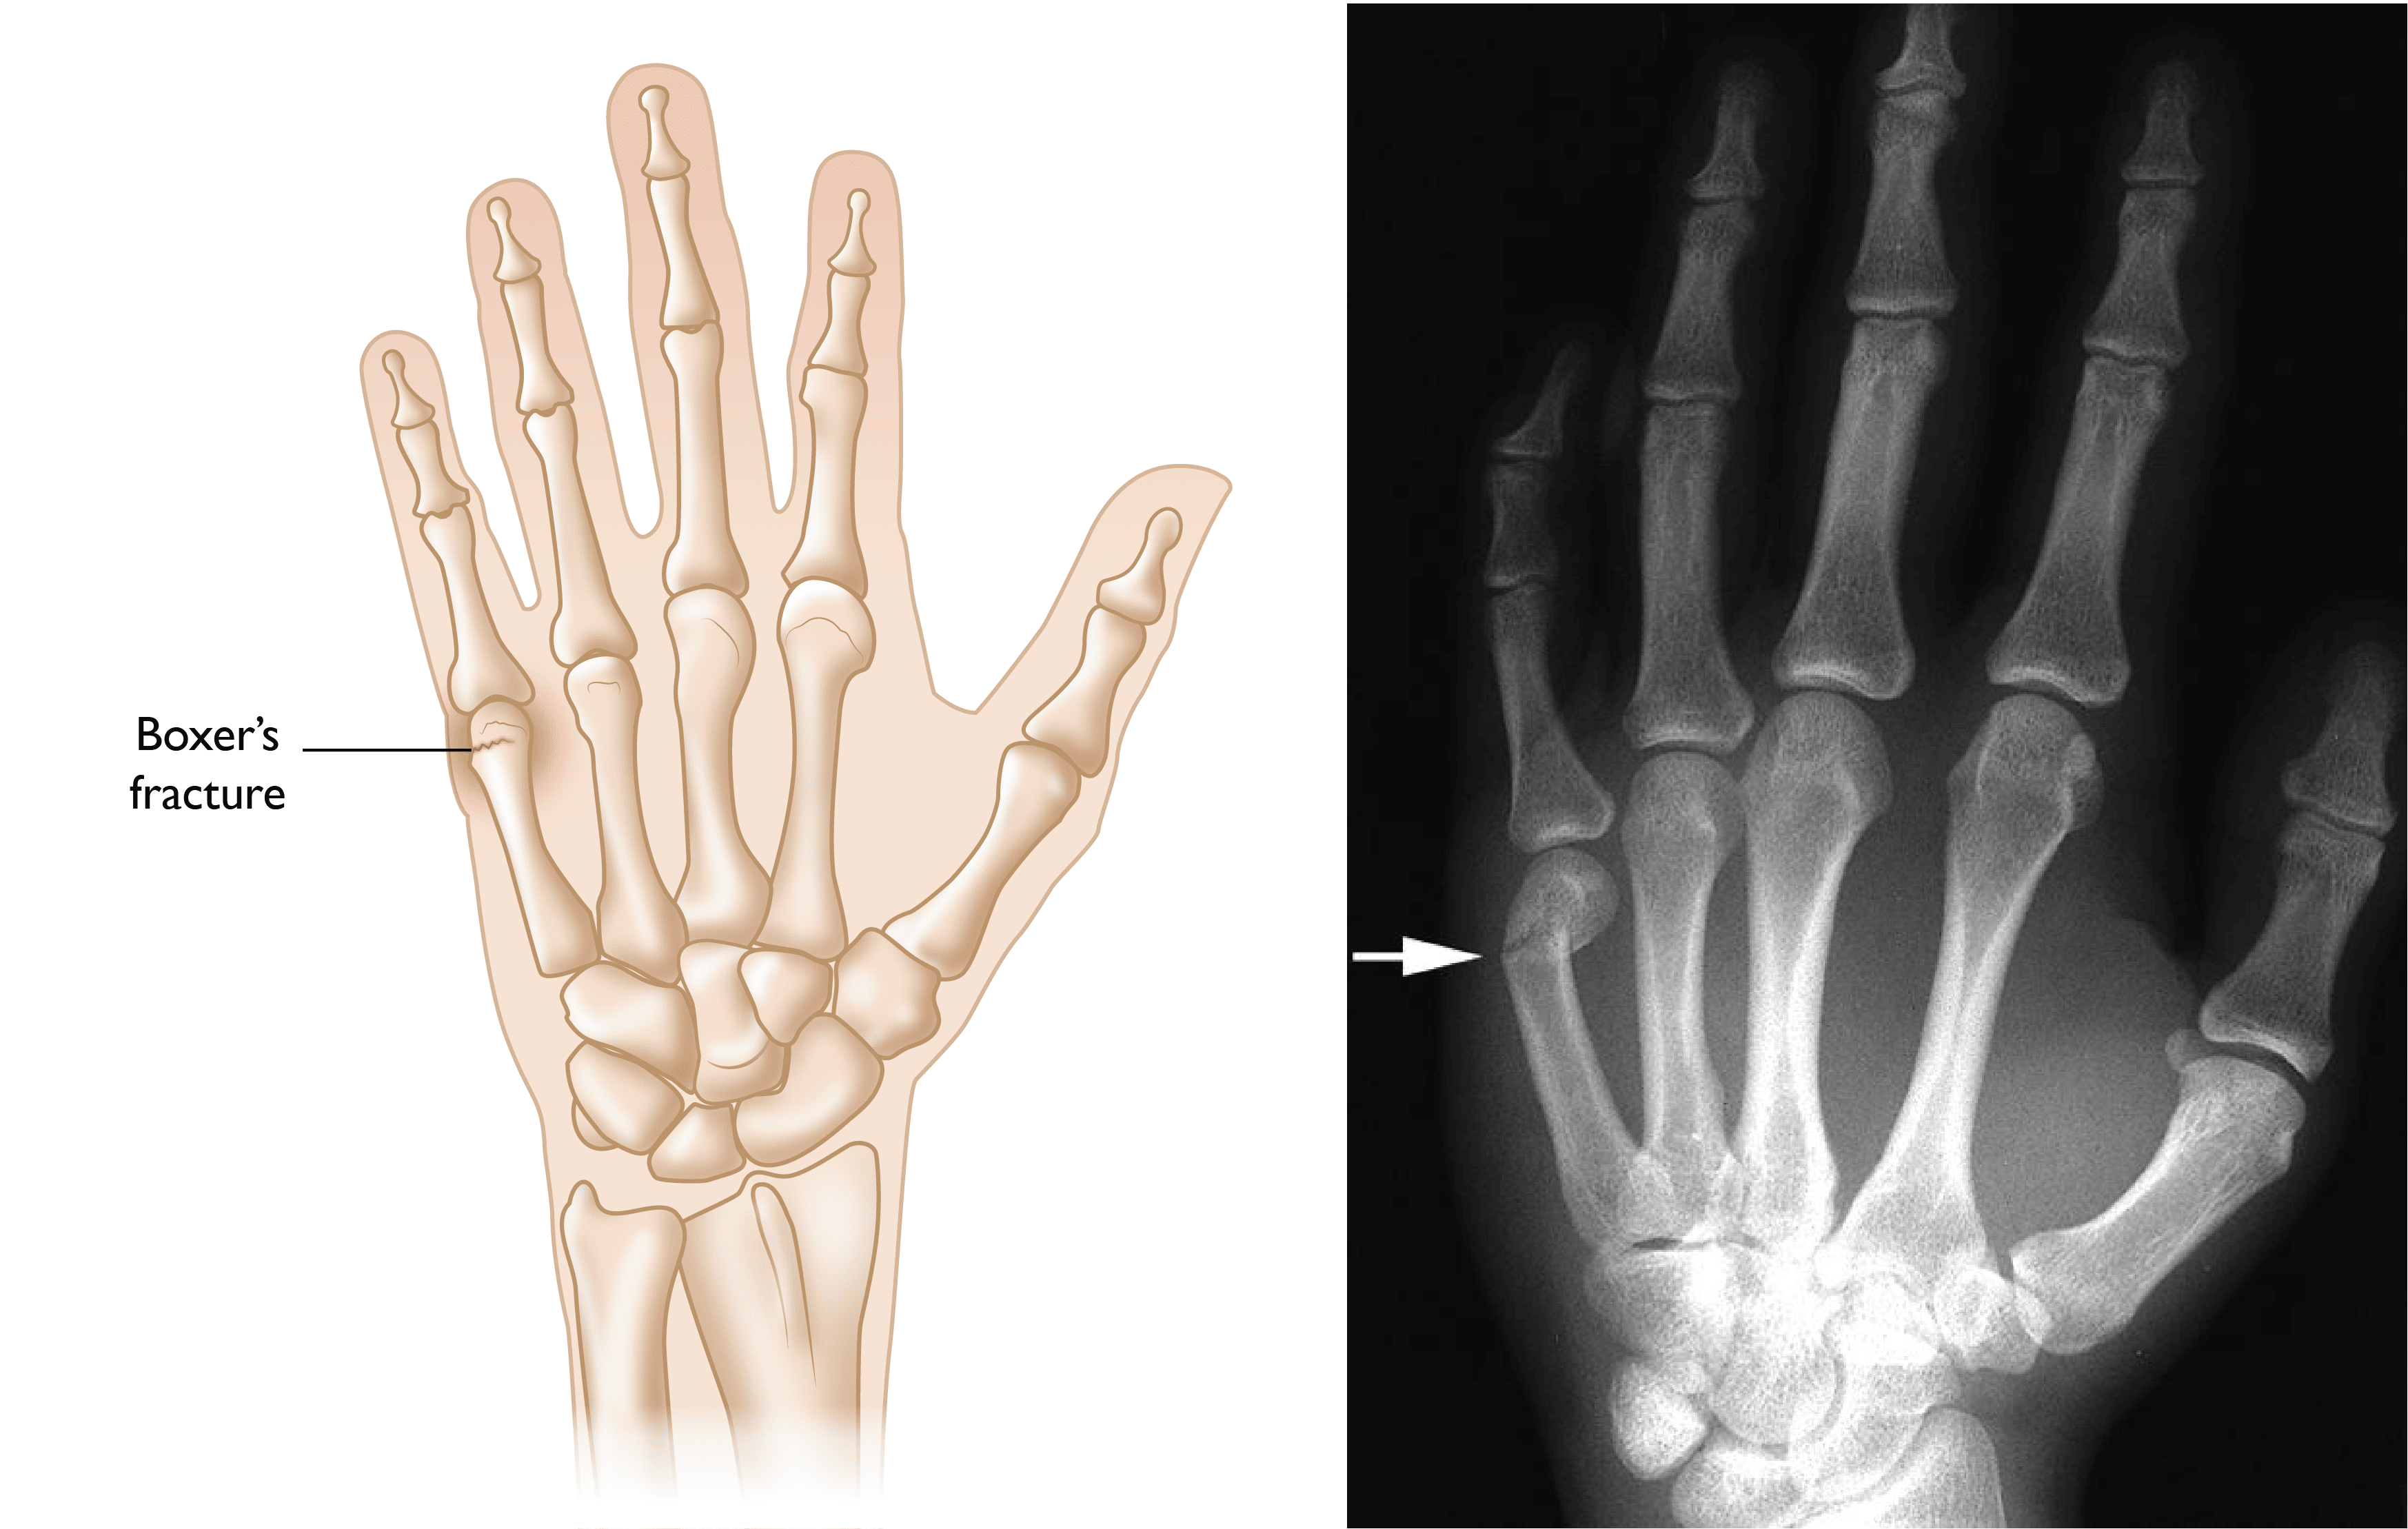

• Your hand strikes a hard object. Fractures of the metacarpal bone that attaches your little finger to your hand, which account for about one-third of all hand fractures in adults, are typically caused by a punching force (these are known as "boxer's fractures").

Boxer's Fracture

(Left) Illustration and (Right) X-ray of a “boxer’s fracture” in the fifth metacarpal. This common hand fracture can cause the knuckle on the affected finger to appear sunken in or angulated.

Right: Reproduced from Johnson TR, Steinbach LS (eds): Essentials of Musculoskeletal Imaging. Rosemont, IL American Academy of Orthopaedic Surgeons, 2004, p. 347.